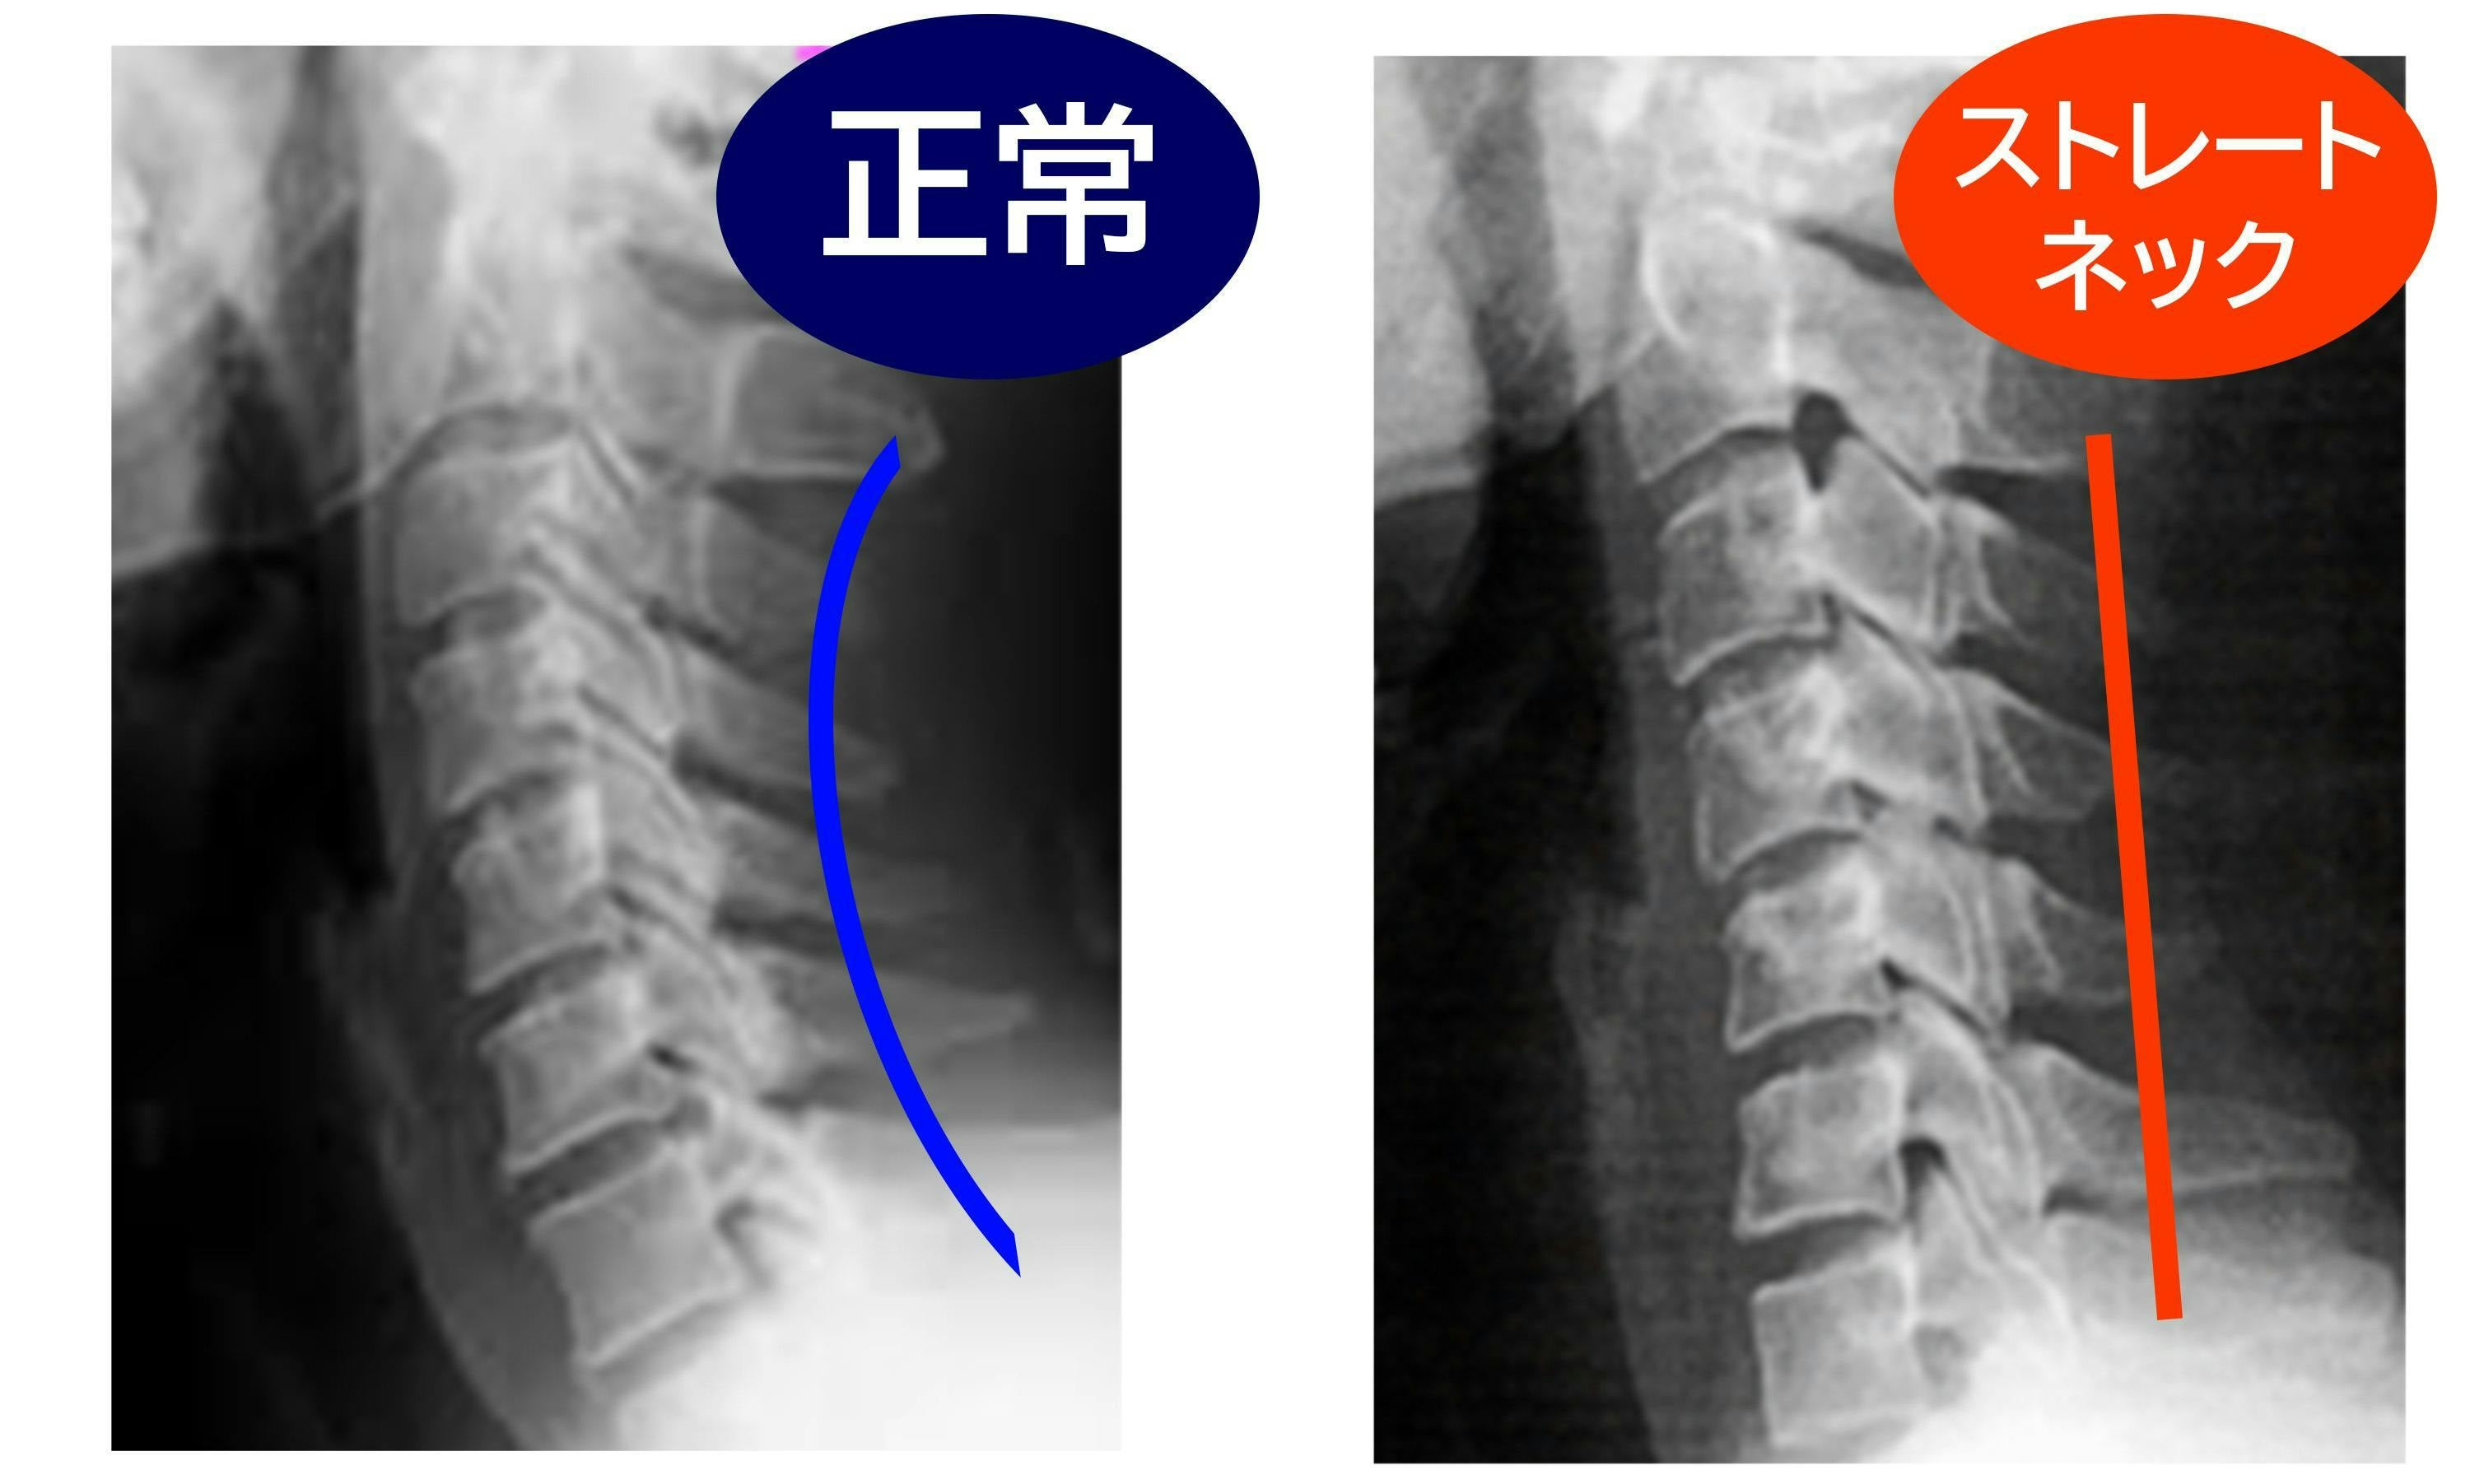

健康な頸椎曲線をどんな体制でも保つことができたら。僕以外にも欲している人は多いのではないでしょうか。そんな夢のような枕が、この度完成しました。

小さな画面の小さな文字や動画を追っているうちに、気づけば前かがみの姿勢をずっと続けていたということ、きっと誰でも経験があると思います。

現代に蔓延するストレートネックを何とかしたい。私は鍼灸師・柔道整復師の先生に監修に入っていただき、快眠枕「安眠二郎」の商品開発に乗り出しました。

誰でも簡単に健康な頸椎曲線を目指せる快眠枕の開発を進めました。